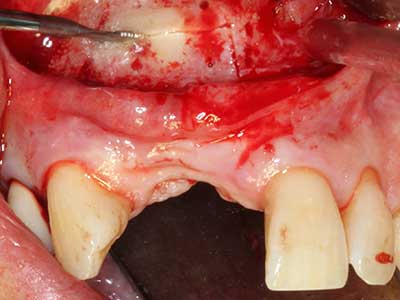

Bone tissue is not simply a mineral structure but also contains a substantial proportion of collagen fibres. This means it not only has good compressive strength but also a degree of flexibility, which can be taken advantage of when performing bone augmentations. In the classical expansion procedure using bone splitting, the atrophied alveolar ridge is split longitudinally and carefully expanded after reaching an adequate osteotomy depth (Fig. 13-16), ideally without substantial removal of the periosteum (Brugnami, Caiazzo et al. 2014, Stricker, Fleiner et al. 2014). Screw and plate systems with increasing expansion distance have proven effective in separating the two bone lamellae while remaining below the fracture threshold. In general, residual bone widths of at least 3–4 mm are required (Chiapasco, Zaniboni et al. 2006) to guarantee adequate flexibility and sufficient bone coverage of the future implants. If necessary, a vertical relief osteotomy on one or both sides can improve flexibility. A combination with additional augmentation techniques, particularly on the buccal side, has been described as an alternative to the classical technique.